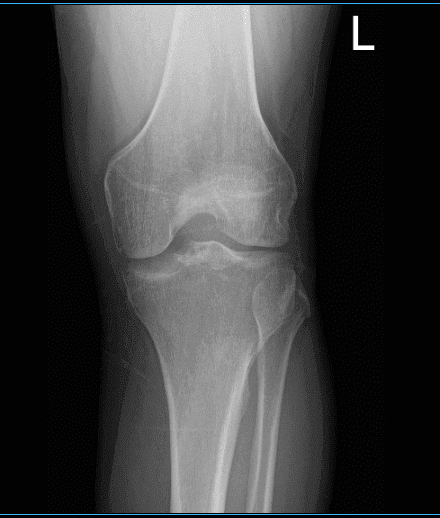

El paciente está aquí con quejas de dolor en la rodilla izquierda. Tiene 26 años y actualmente trabaja como electricista. Se lesionó la rodilla hace tres meses y no sabe exactamente cómo, quizá se la torció accidentalmente. No puede doblar ni alargar la rodilla y está cojeando y sin poder soportar peso en el pie. Está aquí con radiografías en la rodilla izquierda.

Los resultados de las radiografías mostraron que existe un leve estrechamiento del espacio de las articulaciones compartimentales laterales. Hablamos sobre opciones de tratamiento para su condición, incluyendo fisioterapia, resonancia magnética, inyección y cirugía. Acordamos hacer una resonancia magnética de 3 tesla para la rodilla izquierda, él también aceptó empezar la fisioterapia y continuar con la terapia de reposo/hielo/compresión/elevación.